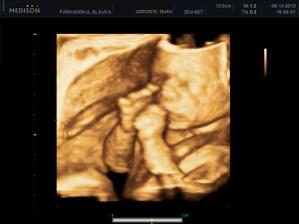

Naše druhé Slniečko